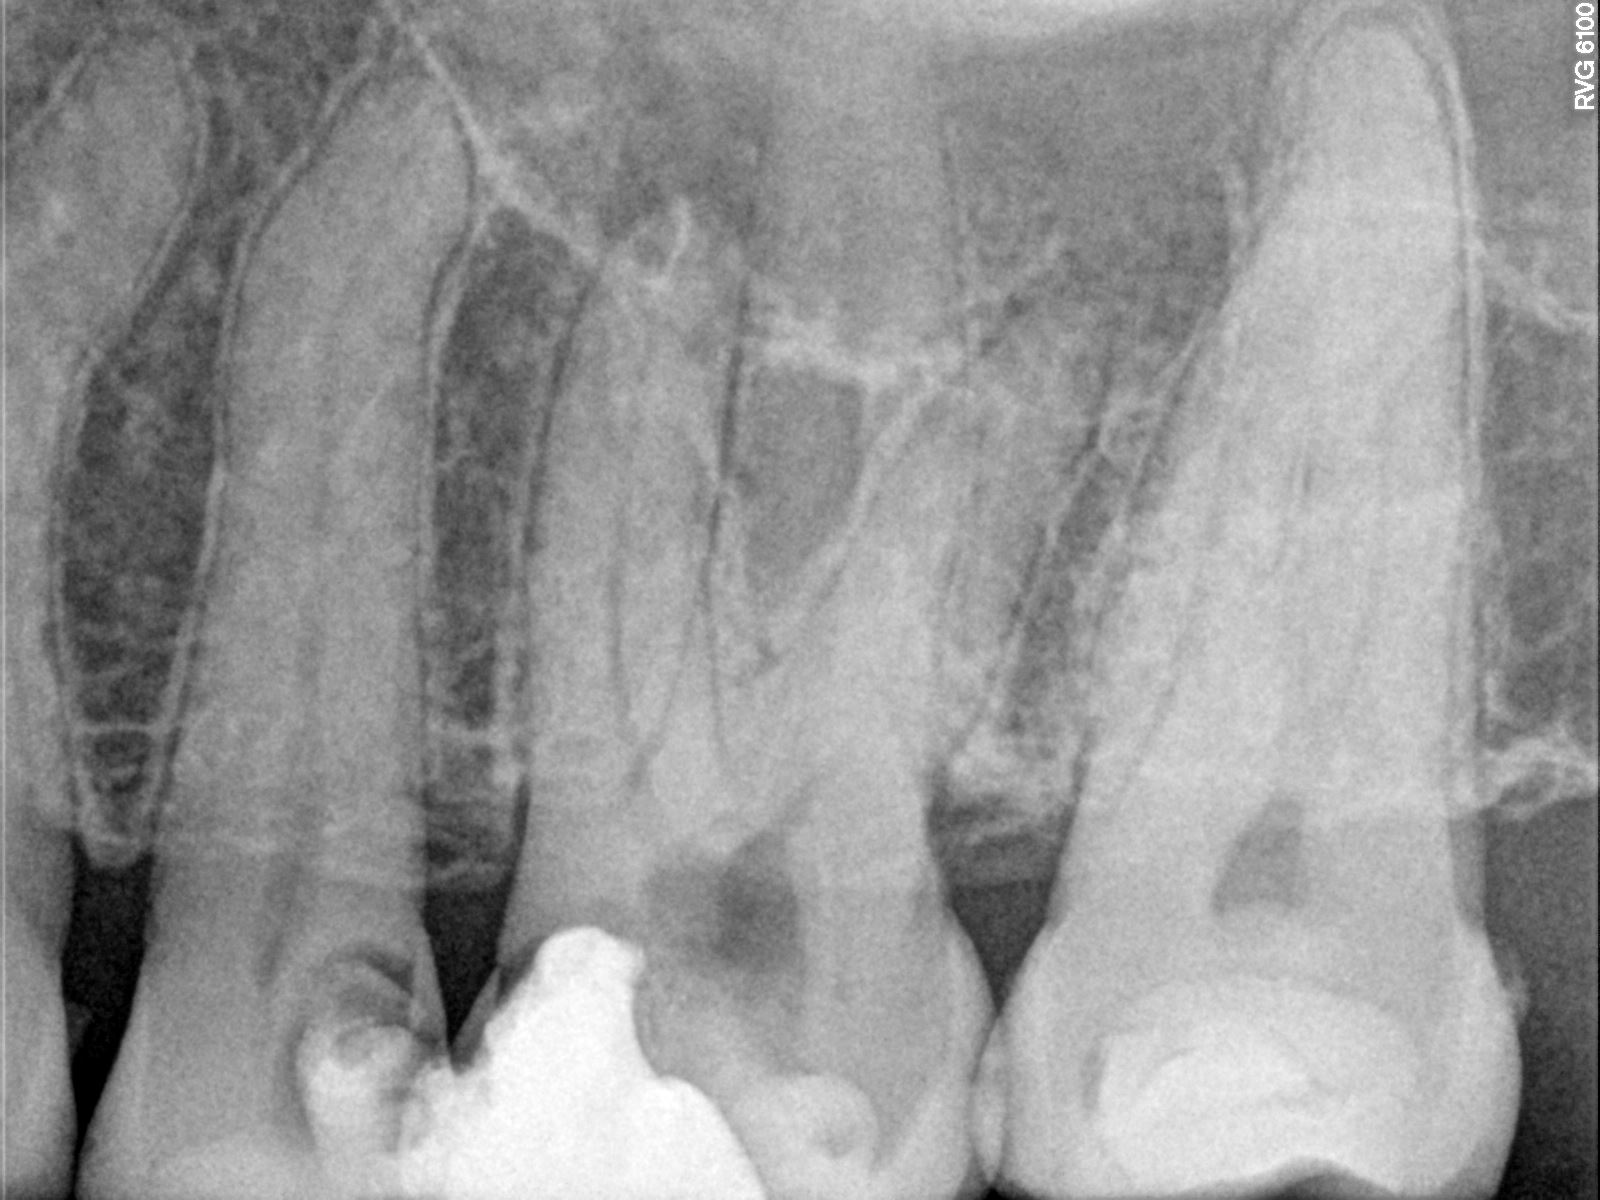

Ce patient de 40 ans, sans antécédents médicaux, a été adressé pour un traitement endodontique de la dent 26. La dent s’est nécrosée en raison d’une reprise de carie. Une obturation provisoire a été mise en place avant le début du traitement endodontique.

Nettoyage et mise en forme :

La longueur de travail a été déterminée à l'aide des limes manuelles 08. Le cathétérisme a été créé à l'aide de limes manuelles 08, 10 et 15. La préparation canalaire a été réalisée avec la lime Procodile Q 25.06 (diamètre 25 et conicité de 6%). Dans la majorité des cas, cette taille est suffisante pour l'ensemble de la préparation, de sorte qu'une seule lime à mouvement alternatif permet de réaliser toute la préparation canalaire. Cela permet d’avoir un protocole efficace et un travail prévisible. Le design de la lime Procodile Q permet une remontée efficace des débris. Il est indispensable au fur et à mesure de la mise en forme de bien éliminer les débris des spires de l’instrument.